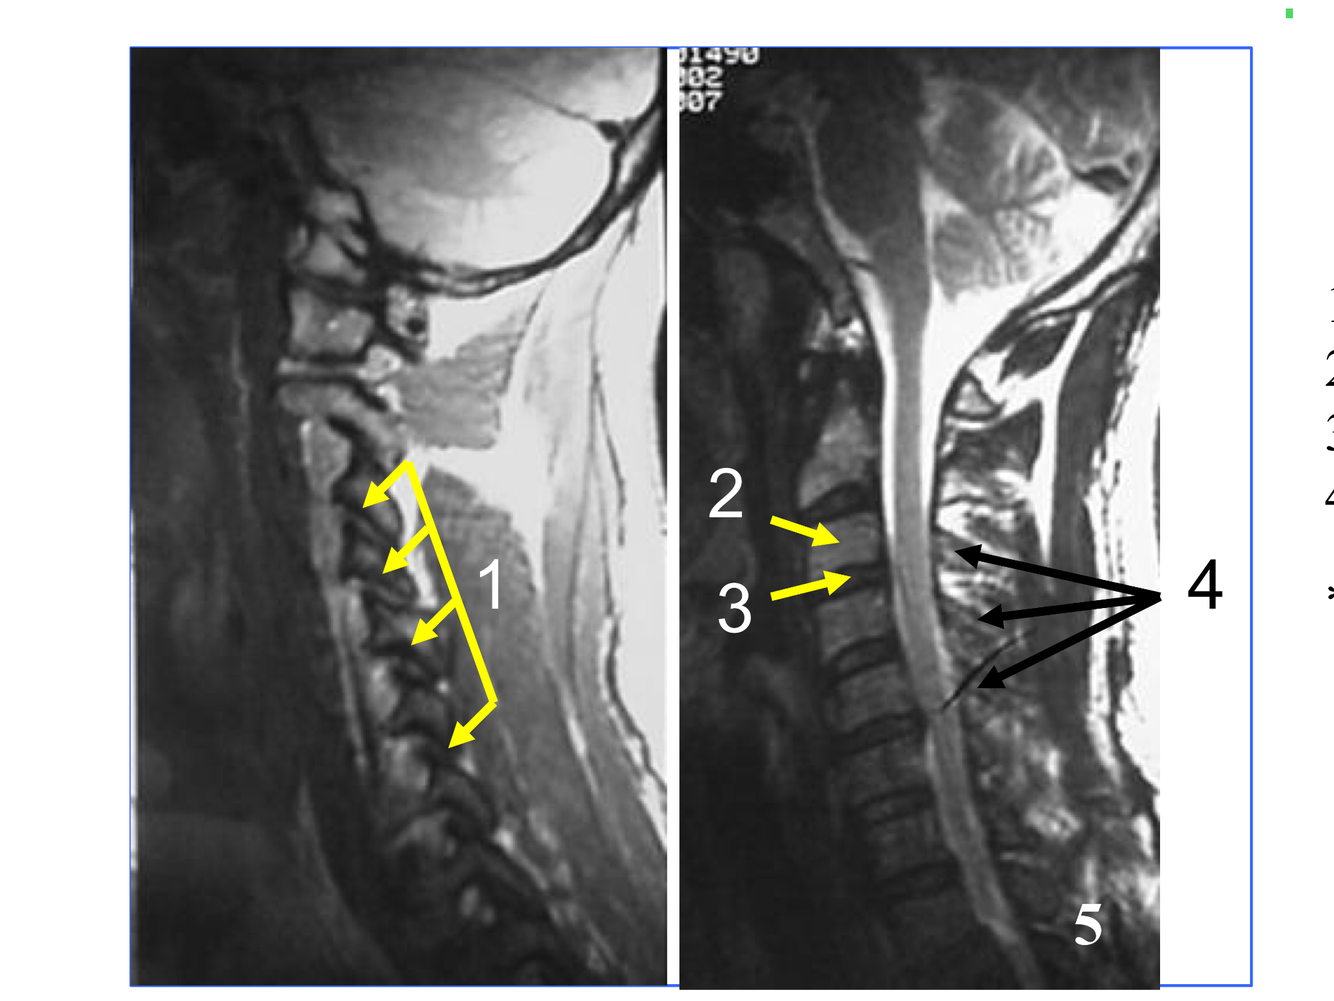

*Appears as streak as it heads fo rmidline in front of the medulla oblongata, to join the Rt vertebral and form the basilar A at the inferior and anterior to the pons.

** At the foramen magnum, entering the posterior fossa of the cranium.

**10. Rt & Lt vertebral arteries**